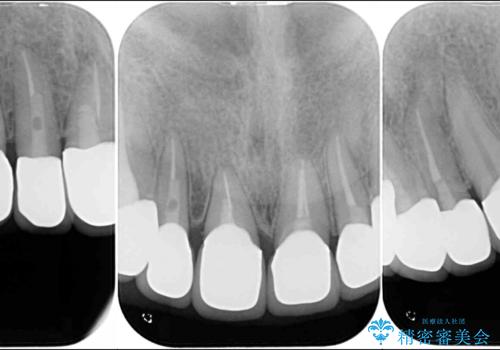

- 前歯のセラミッククラウンの不自然な色調と、虫歯を気にして来院された患者様です。

6歯全てが連結されていたため、外れかけていた右の犬歯は知らぬ間に虫歯が深くにまで進行していました。

深い虫歯の犬歯は、根管治療を行った後に部分矯正を行い、歯周外科処置により環境を整えてから、6歯それぞれのオールセラミッククラウンにて補綴することとしました。

下の前歯がほとんど隠れてしまうほどの深い咬み合わせで、咬合力も強いため、治療期間中は仮歯が外れやすく、ご迷惑をおかけしました。

セラミッククラウン装着後は、とても自然な口元に仕上がりました。